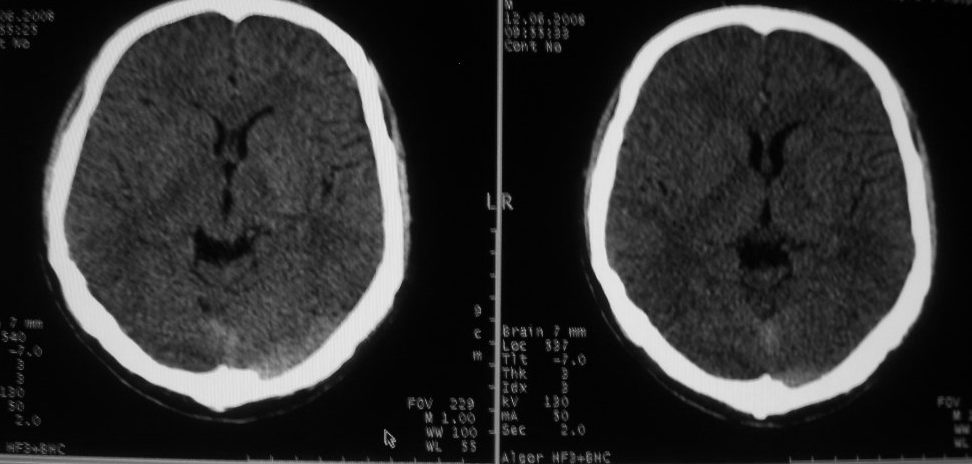

以下是引用守望可可西里在2008-6-13 1:25:00的发言:[br][br] 1.双侧大脑中动脉高密度踌型样接近于全程显示,部分大脑前动脉、基底动脉也呈高密度改变。[br] 2.右侧基底节多发类圆形ct值接近于出血的高密度,边缘模糊。双侧小脑幕及直窦、上矢状窦增宽、模糊。左侧横窦和乙状窦区密度增高、呈云雾状,内缘模糊。[br] 如果这样的表现发生在一个老年人脑部,我们首先会想到是高血压、动脉粥样硬化,就可以很容易得出结论。但这发生在一个20岁年青人的身上,且病程长达半年、临床症状不怎么重,这就比较蹊跷且应该引起高度重视了。[br] 我认为此病人应该是一个血液病患者--双侧大脑中动脉、部分大脑前动脉及基底动脉的高密度改变,只是一个假象:即相对于ct值偏低,只有35的脑灰质而言的相对高密度。而那么多出血改变,则是真正的病变表现。[br] 建议临床进一步进行其他相关的血液、骨髓检查,肝、脾也应该好好检查,应有明显的肿大。

以下是引用zwz在2008-6-13 9:13:00的发言:[br]考虑血管畸形可能,建议增强

以下是引用zjzjr在2008-6-13 8:59:00的发言:[br]考虑血管瘤可能性大,建议增强.